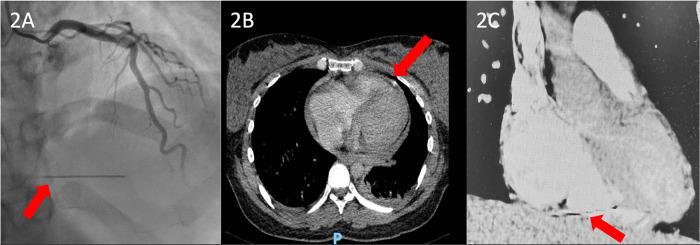

We report the case of a 39-year-old pregnant woman with a history of drug abuse who was admitted to the cardiology department with a diagnosis of tricuspid valve endocarditis. After the multidisciplinary team decided on a conservative treatment with antibiotherapy, the pregnancy was closely monitored. After 4 weeks of treatment, the patient developed extreme thoracic pain and pericardial effusion that was considered infectious and did not require urgent surgery. One month after giving birth to her baby, the patient was admitted to our hospital for the completion of the preoperative protocol. During this admission, multimodal imaging revealed a penetrating metallic foreign body in the wall of the right ventricle. The patient was finally admitted to the Cardiovascular Surgery Unit, where she underwent surgical removal of the foreign body and a complex tricuspid valve repair. The postoperative course was uneventful, and our patient was discharged from the ICU 2 days later.

我们报告了一例39岁有药物滥用史的孕妇,她因诊断为三尖瓣心内膜炎而入住心内科。在多学科团队决定采用抗生素进行保守治疗后,对该孕妇进行了密切监测。治疗4周后,患者出现极度胸痛和心包积液,考虑为感染性,无需紧急手术。在生下婴儿一个月后,患者因完成术前方案而入住我院。在此期间,多模态成像显示右心室壁有一个穿透性金属异物。患者最终入住心血管外科病房,在那里接受了异物手术取出及复杂的三尖瓣修复。术后过程顺利,患者于2天后从重症监护病房出院。